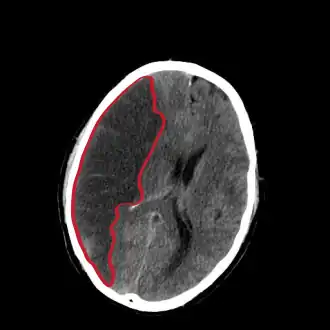

![]() Компьютерная томограмма головного мозга, демонстрирующая инфаркт в правом полушарии головного мозга (зона инфаркта обведена красным.) | |